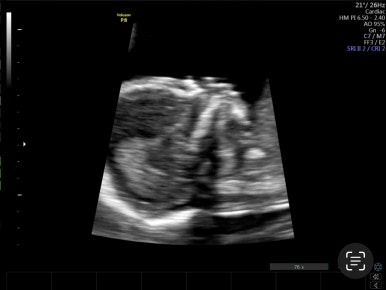

21주 1일

정밀초음파로 외형, 장기 등이 이상이 없는지 확인하는 시기이다.

머리부터 발끝까지 꼼꼼하게 검사를 하게 된다!

손발 등 너무 정교하게 생겨서 너무 신기하다!